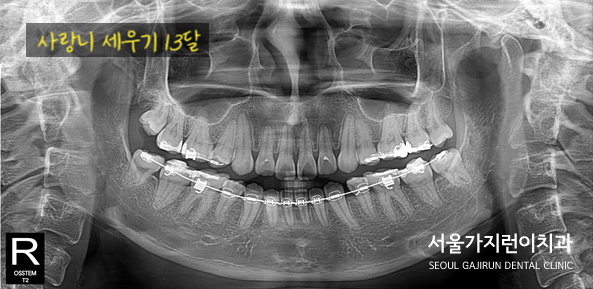

그렇게 사랑니 세우는 치아교정 과정을 보시면,

1달째와 13달때 차이가 확연히 나는 것을 볼 수 있는데요. 사랑니의 뿌리와 모양이 온전하다면 위와 같은 과정을 통해 사랑니를 세워 어금니로 사용할 수도 있겠습니다. 이후 교정이 완료된 모습은 바로 아래사진인데요.

구치부 교합이 안정화 된것을 볼 수 있는데다 추가적인 발치 없이 사랑니를 바로 세워 어금니까지 얻어본 모습으로 치료를 마쳤습니다. 환자분의 경우 나머지 부분에 대한 교정치료는 거부하셨기때문에 적정 선에서 치료를 중단하셨는데요. 환자마다 상황이 다르기 때문에 확답을 드릴 수는 없지만 사랑니 직립을 원하는 경우, 저희 서울가지런치과 교정과 의원을 방문해주시면 성심껏 답변해드릴 수 있으니 참고해 주시면 되겠습니다.